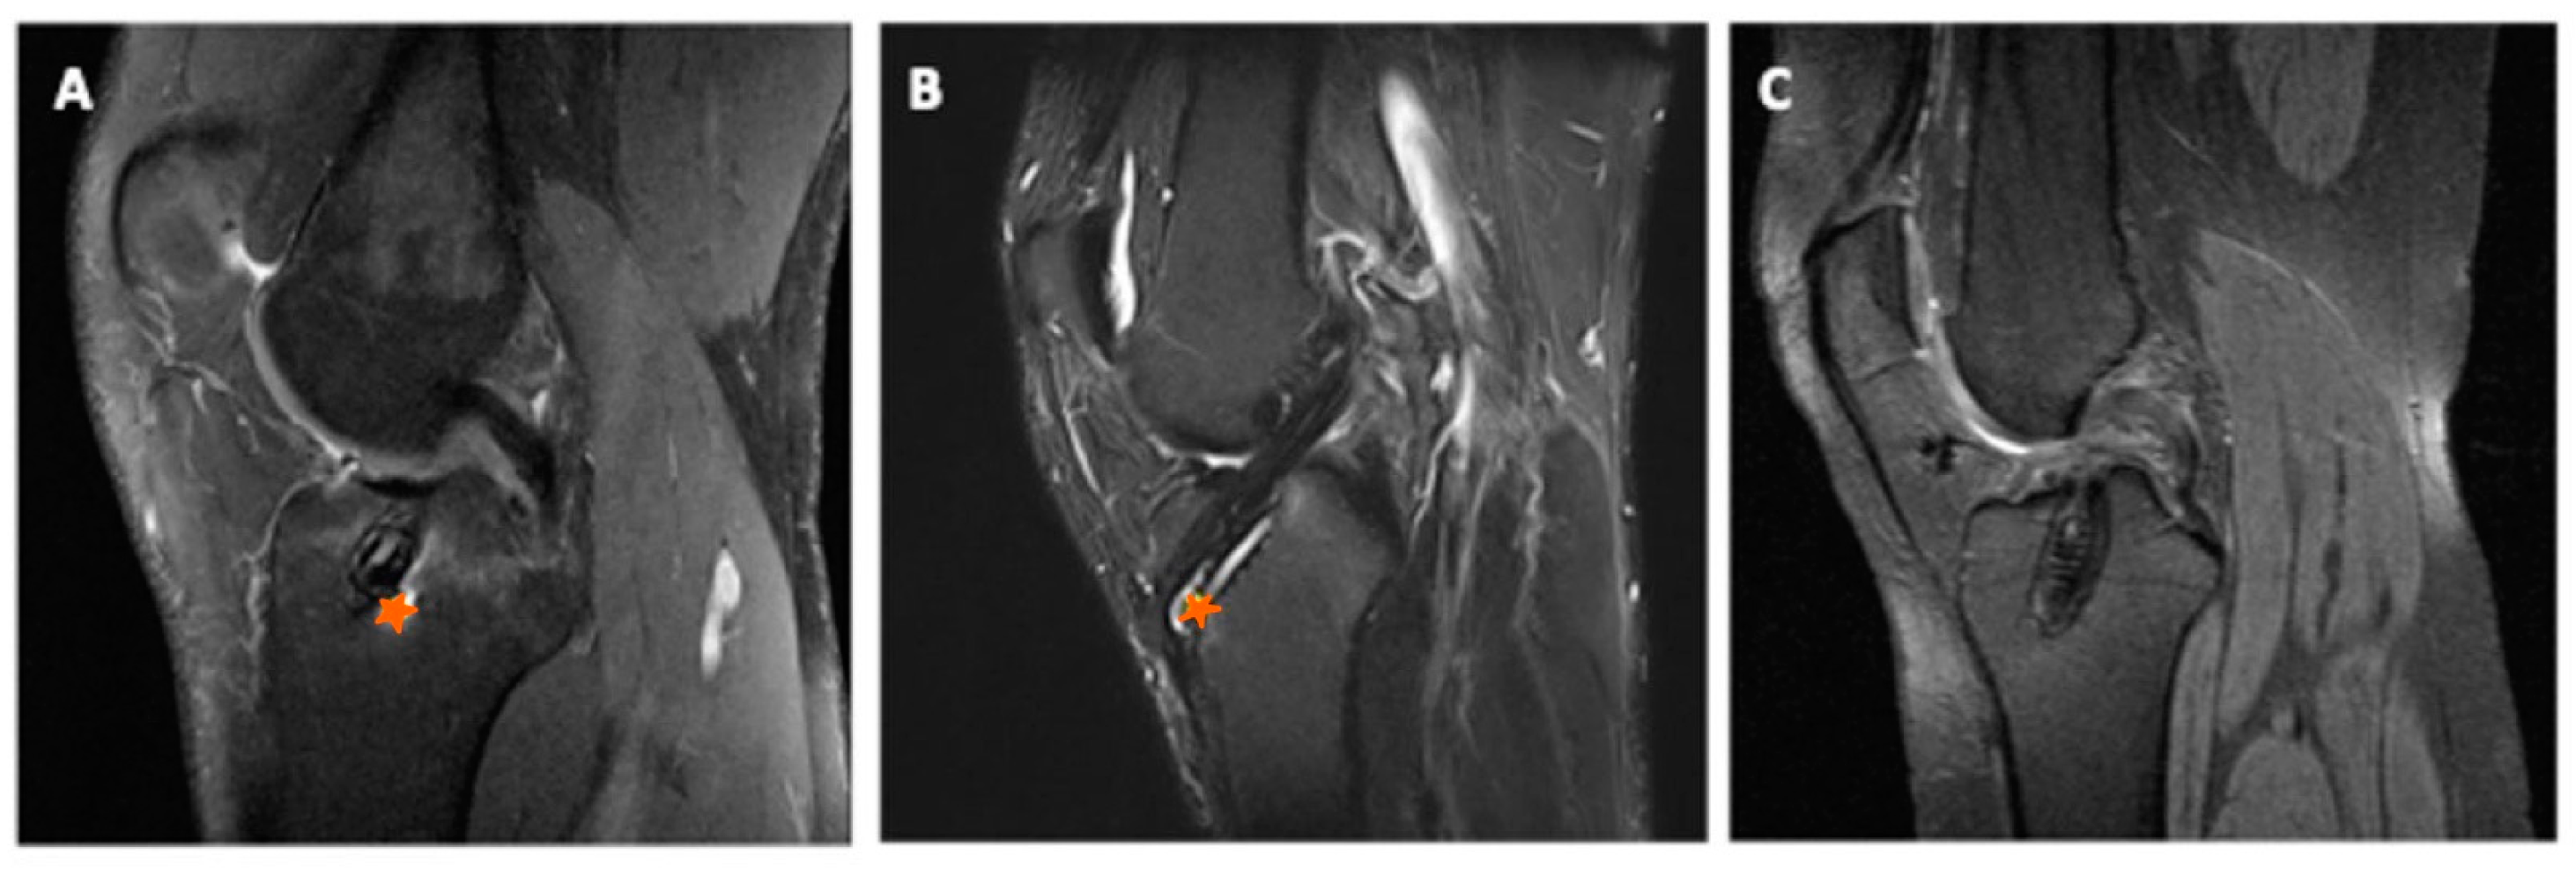

3.3. Radiographic Evaluation